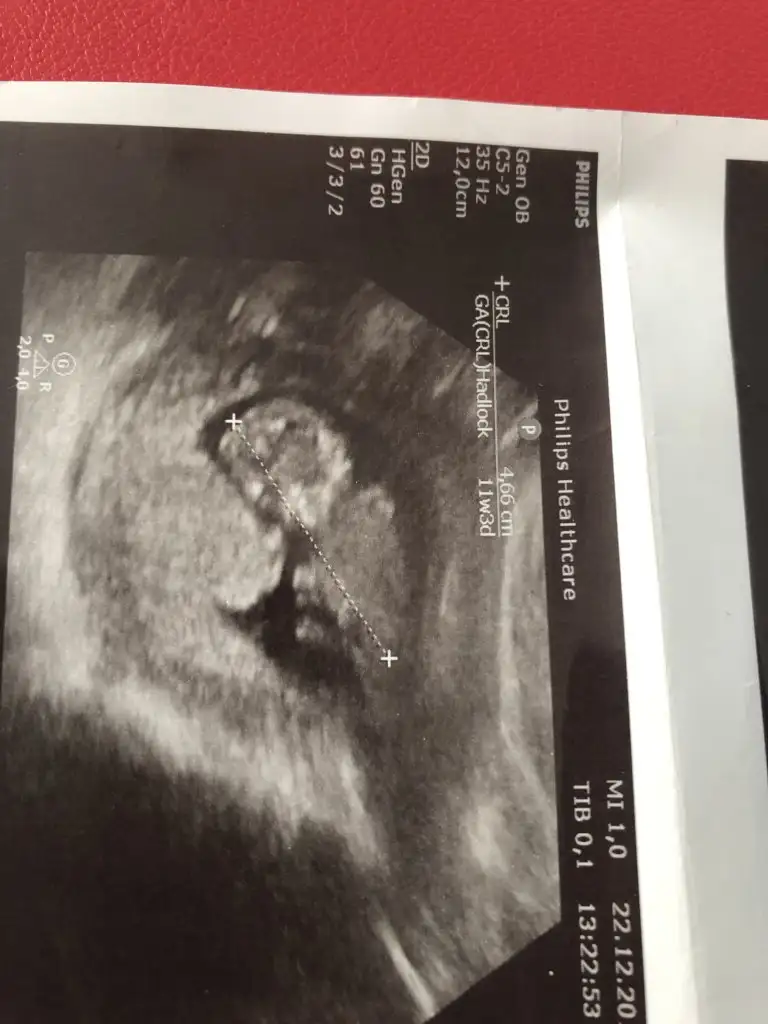

birde bu şekilde var canımNet degil gördüğüm diklik nub ise erkek gibi ama eminde değilim başka usg varmı 11 yada 12 hafta

Bu daha kötü net değil cnmbirde bu şekilde var canım